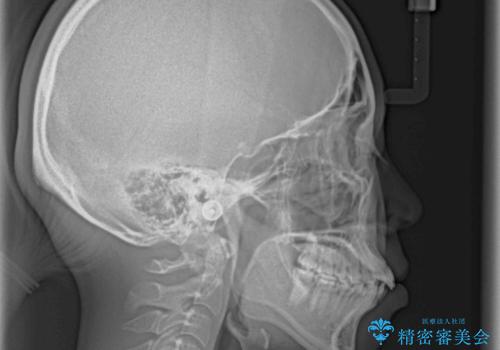

口元を積極的に引っ込めるために、上下左右の小臼歯4本を抜歯することとしました。

4本の歯を抜歯したことで、飛び出していた口元が引っ込み、横顔が大きく改善されました。